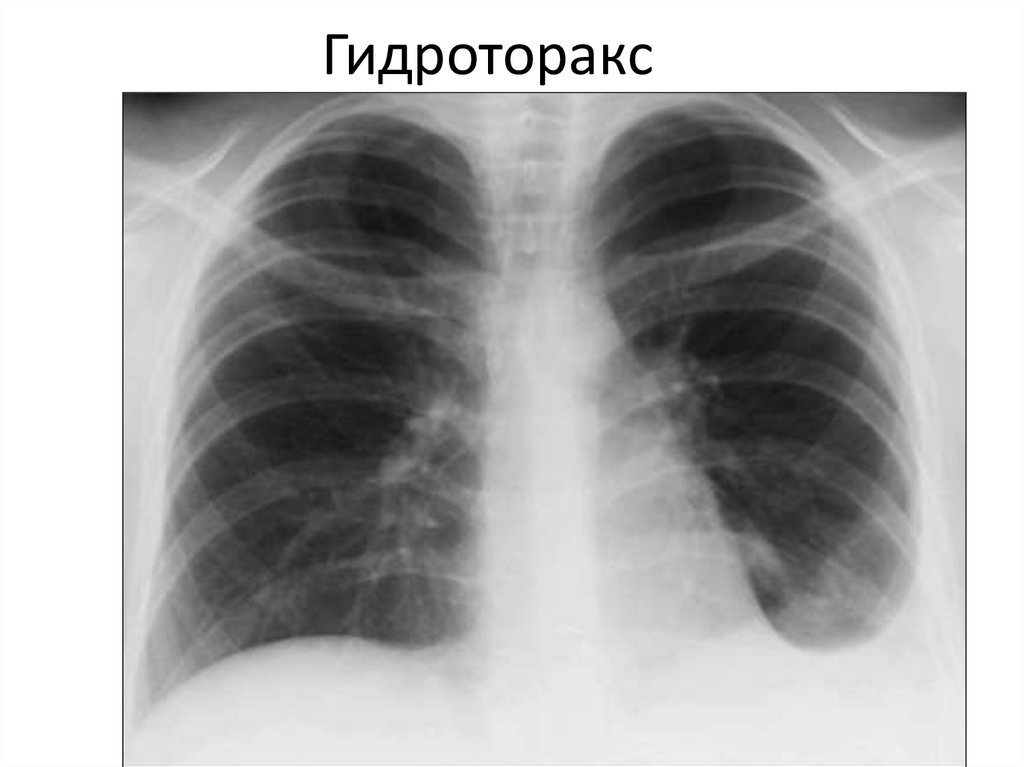

Гидроторакс

Пневмоторакс Гидроторакс